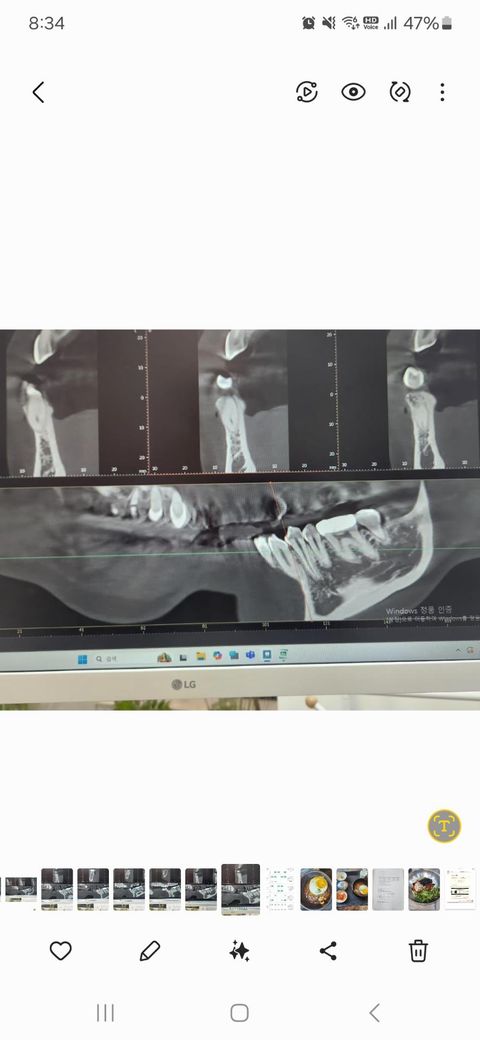

잇몸치료한다고 하악 잇몸마취를 했는데 19일 4시에 치료가 끝났는데 지금까지 어금니 잇몸쪽이 얼얼하고 볼이 당겨지는 느낌이 있습니다 어제는 치과가니 볼이랑 턱쪽을 마사지하듯 둥글게 문지르면서 확인하더니 멍울 만져지는게 없다면서 염증이 있는거도 아니고 걱정하지 말라고 함 오늘도 나아지는게 없어서 치과가서 ct를 찍었는데 하악치조골 신경이 있는데 그게 끊어지거나 한게 없어서 손상된게 없다고 대신 파랗게 동그라미친 부분의 뼈골밀도가 낮아서 마취가 잘되고 그로인해 얼얼한 느낌이 있을수 있다고 시간 지나면 회복된다고 합니다 안심해도 되는 상태일까요? Ct사진 같이 올리는데 의사말을 신뢰해도 될까요? 판독도 해주세요

• 2번 째 사진